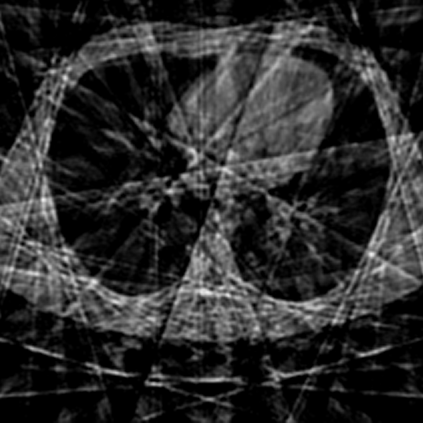

Sparse-view computed tomography (CT) -- using a small number of projections for tomographic reconstruction -- enables much lower radiation dose to patients and accelerated data acquisition. The reconstructed images, however, suffer from strong artifacts, greatly limiting their diagnostic value. Current trends for sparse-view CT turn to the raw data for better information recovery. The resultant dual-domain methods, nonetheless, suffer from secondary artifacts, especially in ultra-sparse view scenarios, and their generalization to other scanners/protocols is greatly limited. A crucial question arises: have the image post-processing methods reached the limit? Our answer is not yet. In this paper, we stick to image post-processing methods due to great flexibility and propose global representation (GloRe) distillation framework for sparse-view CT, termed GloReDi. First, we propose to learn GloRe with Fourier convolution, so each element in GloRe has an image-wide receptive field. Second, unlike methods that only use the full-view images for supervision, we propose to distill GloRe from intermediate-view reconstructed images that are readily available but not explored in previous literature. The success of GloRe distillation is attributed to two key components: representation directional distillation to align the GloRe directions, and band-pass-specific contrastive distillation to gain clinically important details. Extensive experiments demonstrate the superiority of the proposed GloReDi over the state-of-the-art methods, including dual-domain ones. The source code is available at https://github.com/longzilicart/GloReDi.